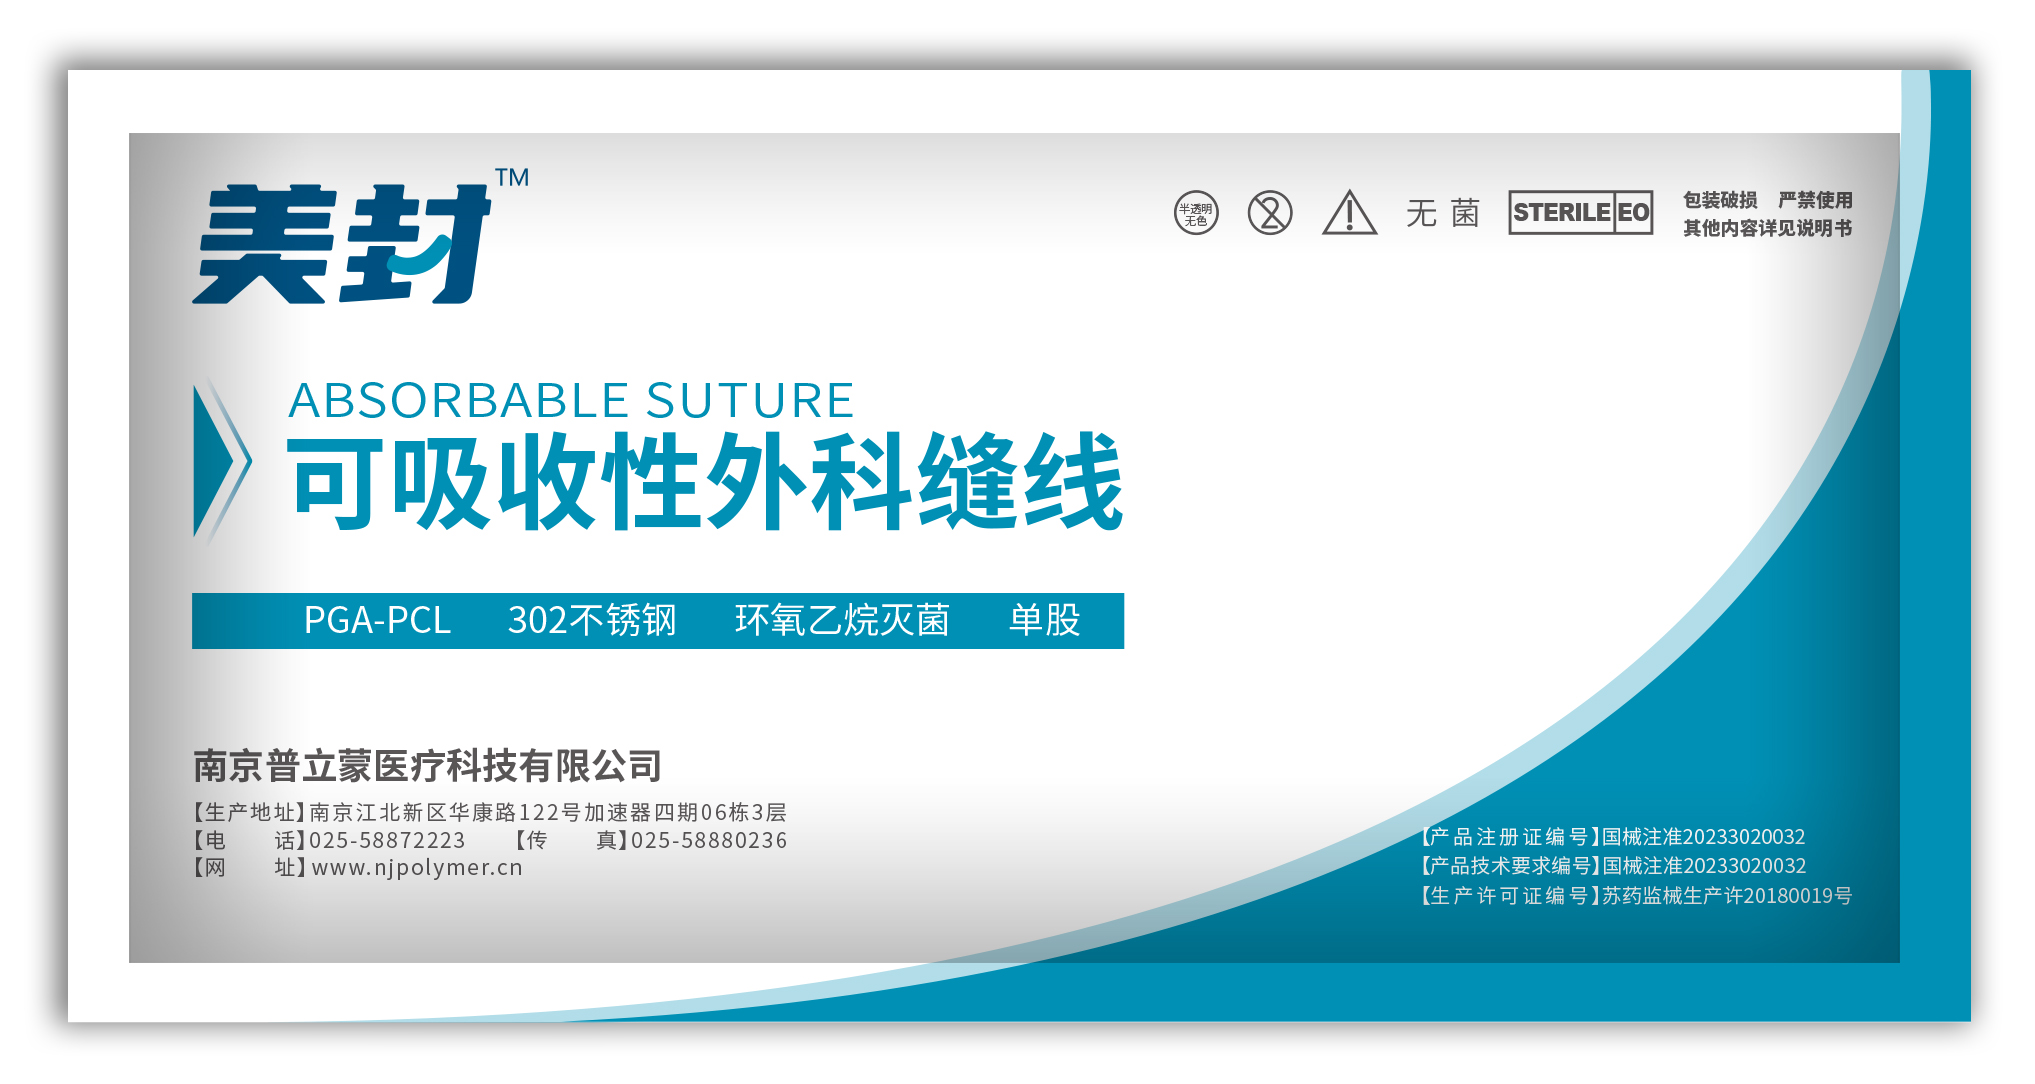

非吸收外科缝线